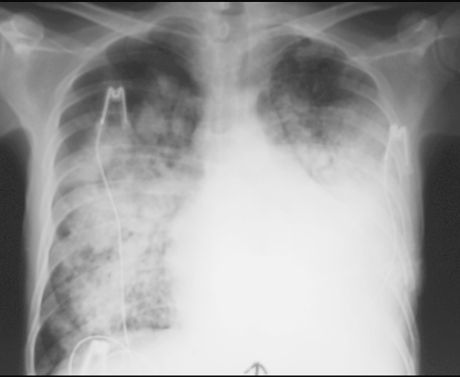

OBRZĘK PŁUC

RTG